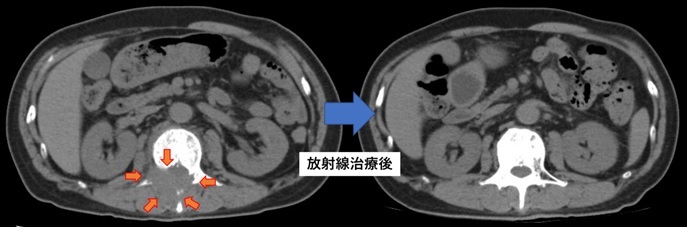

転移性骨腫瘍

肺がん腰椎転移。転移巣が腰椎を溶かし、骨外に進展している。

放射線治療により疼痛が緩和され、かつ腰椎転移は消失し骨が修復された。